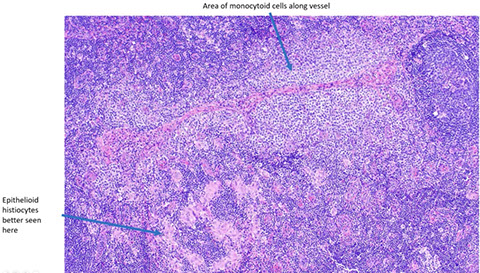

Toxoplasma lymphadenitis. Has lots of reactive follicles, intact capsule with patent subcapsular sinus getting closer to hilum. Increased follicles almost back to back, but have well-preserved and well-defined mantle zones and preservation of the interfollicular areas. There are lots of pinkish cells, which are epithelioid histiocytes which surround and encroach upon involved follicles [3]

Epithelioid histiocytes in toxoplasma infection [3]

Classic triad of monocytoid cells, enlarged follicles with reactive germinal centers, and epithelioid histiocytes encroaching germinal centers in Toxoplasma [7]